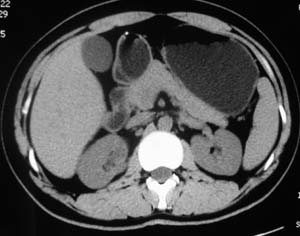

以下是引用子期在2010-3-19 20:47:00的发言:[br]血管畸形的ct增强应该有明显强化,本例并不相符合。本例双肾局部的略低密度影,累及肾盂,局部皮质明显变薄、内陷,增强扫描有轻度的强化,应考虑为炎性病变,患者为年轻男性,累及双肾的感染以结核较常见,可以没有明显的临床症状,尿中有时候也并不能查出什么;肾脓肿常有明显感染中毒症状,本例不符,另外一般的肾盂肾炎或肾小球肾炎通过小便就可确诊,其它还不能排除的是黄色肉芽肿性肾盂肾炎,然而单凭ct一般也很难鉴别。